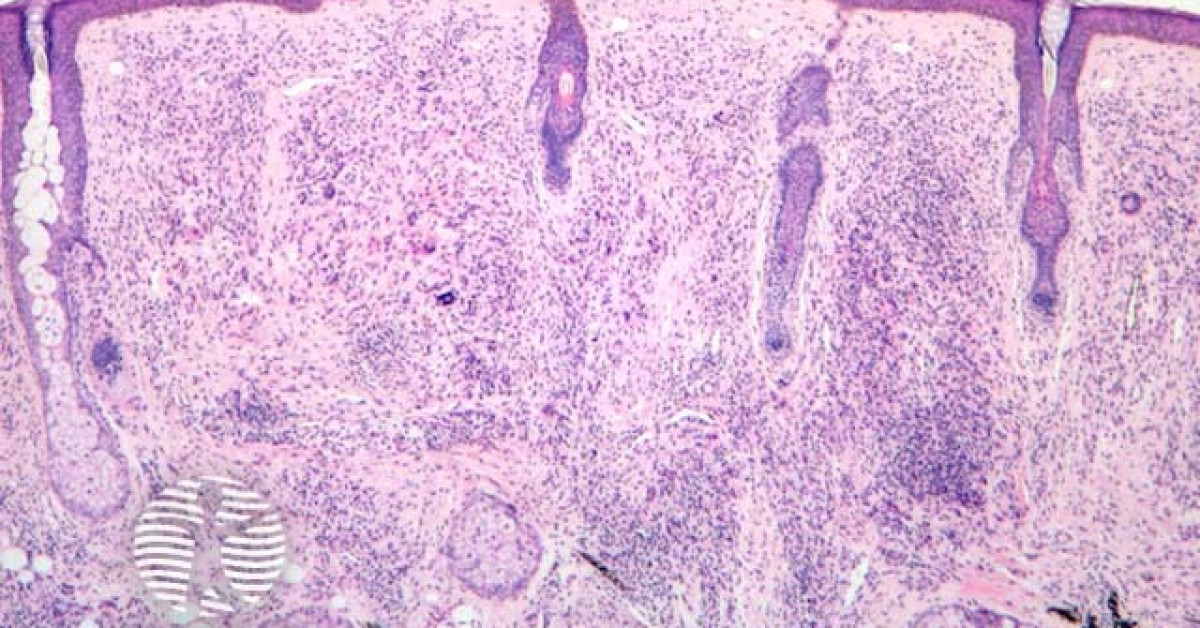

Diagnose

Die Diagnose ergibt sich aus den klinischen Befunden.